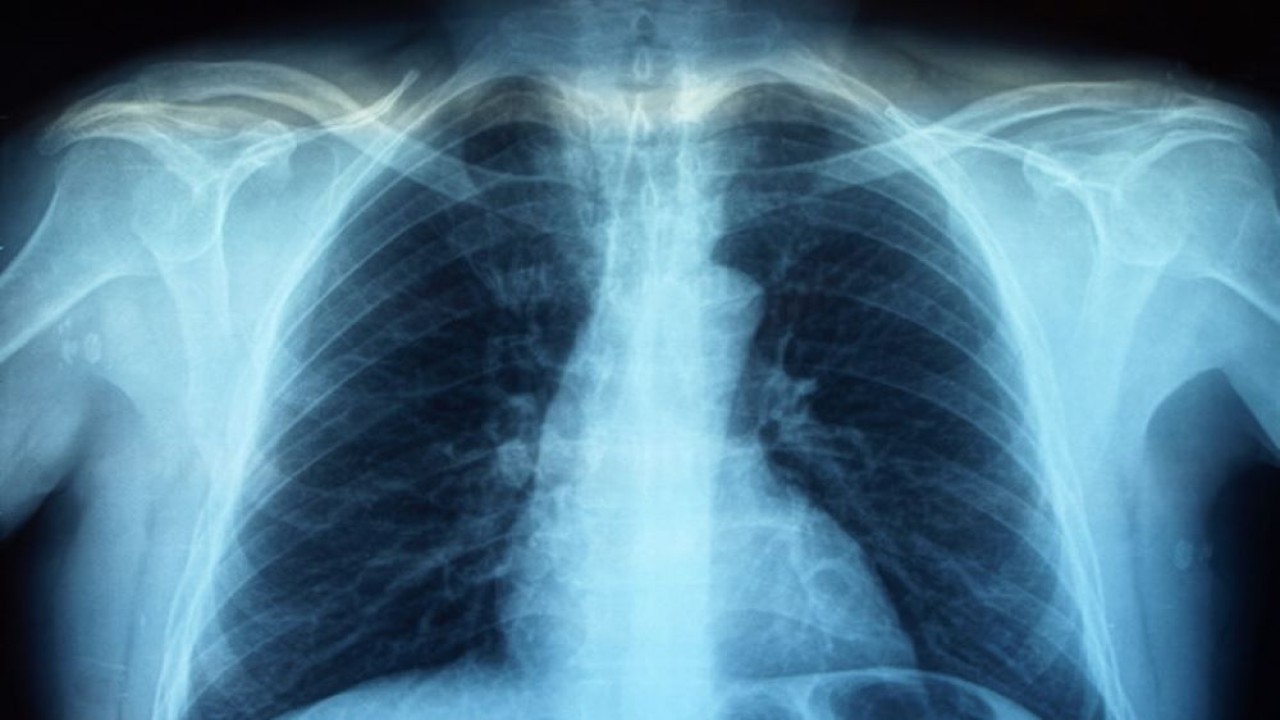

Diketahui, penyakit Legionnaires adalah jenis radang paru-paru atau pneumonia yang disebabkan oleh bakteri legionella.

Penyakit Legionnaires pertama kali terdeteksi pada 1977 sebagai pemicu wabah pneumonia akut pada 1976 di sebuah gedung pertemuan di Amerika Serikat (AS).